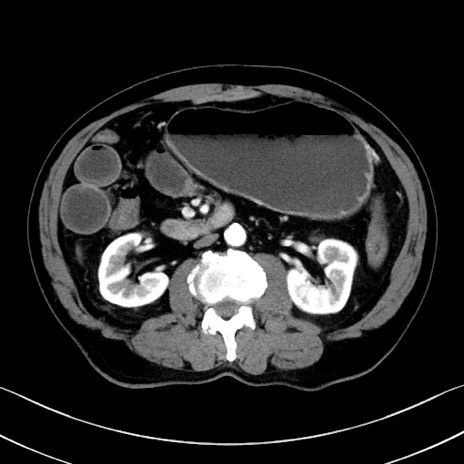

症例35(横断像)

【症例】70歳代 男性

【主訴】腹部膨満、嘔吐

【現病歴】昨日より腹部膨満感出現。本日増悪し、仙痛出現。嘔吐あり、受診。

【既往歴】糖尿病、胆摘後

【身体所見】BP 149/80mmHg、HR 74/min、BT 35.9℃、腹部:膨満、軟、圧痛なし。腸雑音減弱あり。上腹部正中切開瘢痕あり。

【データ】WBC 13500、CRP 1.72